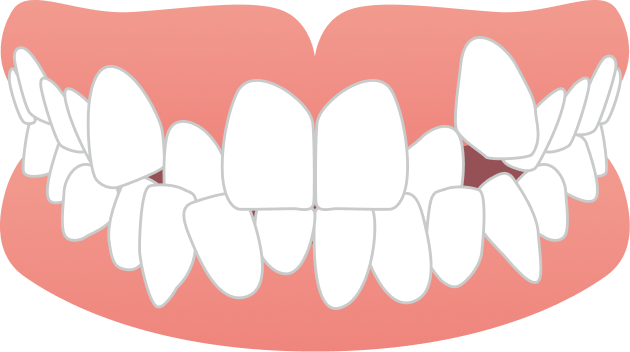

30代男性 出っ歯とガタガタが気になる

30代男性の患者さまで、上の前歯の前突感とガタつきを主訴にご相談に来院されました。目立たず、日常生活への負担をできるだけ抑えながら治療を進めたいというご希望を踏まえ、当院で専門的に行っているマウスピース矯正にて治療を開始しました。

治療では、歯列全体のバランスと噛み合わせを考慮しながら計画を立て、抜歯を行うことなく、マウスピースのみで治療を進めました。治療期間は1年9ヶ月で、見た目の印象が大きく改善するとともに、機能的にも安定した噛み合わせが得られています。

自然な口元と噛みやすさの両立を実現できた症例です。

BEFORE